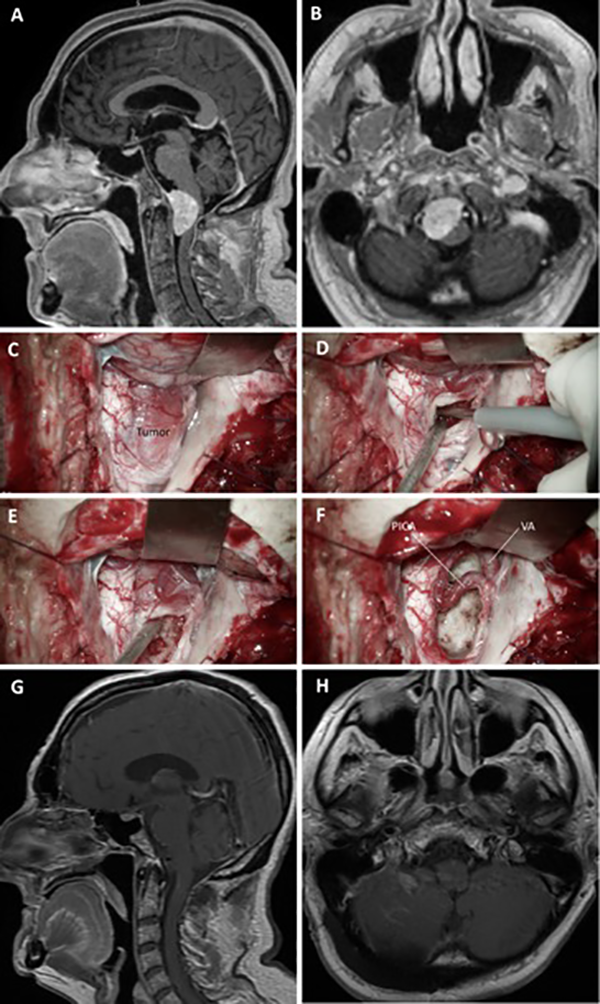

Figura 13. Meningioma del foramen magno. A-B: RM preoperatoria; C-F: Hallazgos intraoperatorios; G-H: RM postoperatoria.